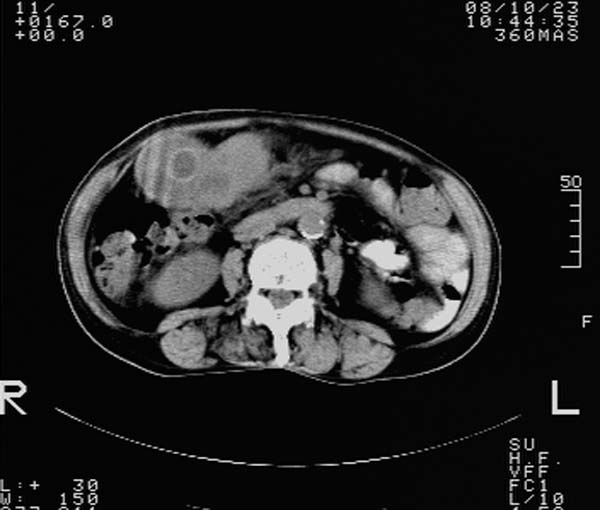

f,67y。反复右上腹痛。余无异常。

前五幅未服造影剂。后面图像有上传重复的。请战友们发表意见。

胆囊内结石,胆囊壁不规则增厚,胆囊胃窦区解剖结构欠清晰,楼主提示为少见病,考虑bouveret综合征?黄色肉芽肿性胆囊炎?肝内多发低密度占位,建议增强或b超

bouveret综合征(胆石性十二指肠幽门梗阻)应重点考虑。期待结果!

考虑bouveret综合征?黄色肉芽肿性胆囊炎?肝内多发低密度占位,囊肿?建议增强!